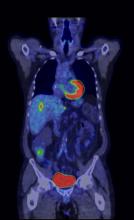

Since entering the market in 2001, PET/CT (positron emission tomography/computed tomography) has come a long way in combining the benefits of individual PET and CT imaging. Last year saw the release of several new innovative technologies, marking improvements on previous generations of PET/CT, such as continuous data acquisition and bed motion, as well as higher image resolutions.